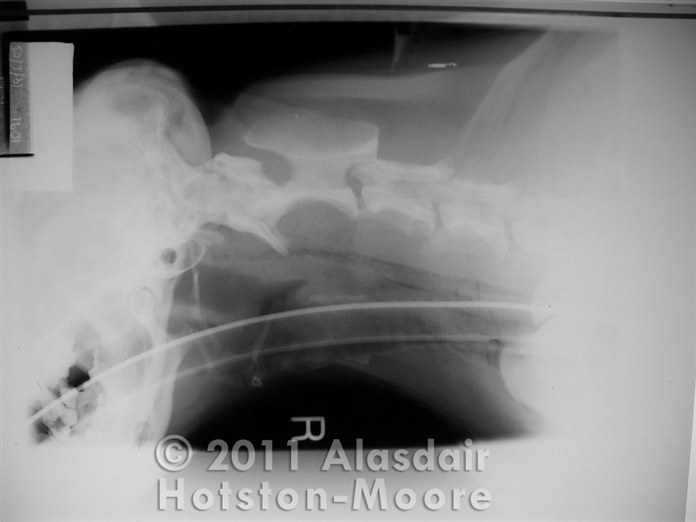

Bath Vet ReferralsLateral cervical radiograph of a dog after a suspected pharyngeal stick injury.

The presence of emphysema in the soft tissues confirms that a significant penetration has occurred that requires cervical exploration.